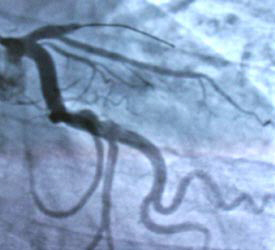

The thin line at the center top is

the catheter shortly after

it was pushed through the clot

blocking the artery.

The

doctor used an arterial stent, a collapsible wire mesh tube, to

reopen the artery.

After the stent was released it

forced the artery open. Blood flow

immediately flowed down the artery

as it should, as shown in the photo above.